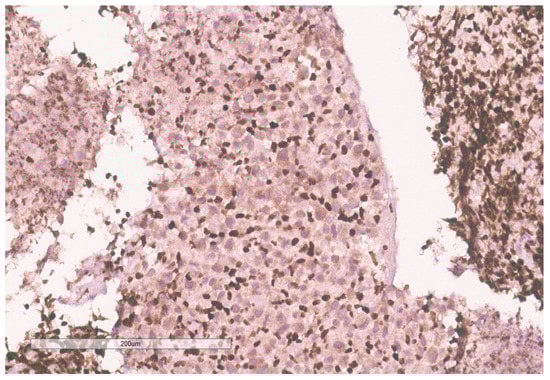

The biopsy of right kidney demonstrated mostly fibrinous material with small fragments of renal parenchyma with interstitial chronic inflammation and no definite tumor. The biopsy of a retroperitoneal lymph node showed high grade tumor composed of discohesive rhabdoid cells with highly atypical nuclei and eosinophilic cytoplasm involving lymphoid tissue with areas of necrosis and neutrophilic inflammation with necrosis and limited viable tumor cells (Figure 7). By immunohistochemistry, the cells were positive for pankeratin (Figure 8) and PAX8 (Figure 9) and negative for CK7, CK20, GATA3, CDX2, TTF1, CAIX, ERG, S100, CD34, CD30, SMA, desmin, OCT3/4 and CD163. The tumor cells showed diffuse loss of SMARCB1/INI-1 (Figure 10). The INI-1 was reviewed by several experienced pathologists that interpreted the stain as negative. While there is some background cytoplasmic and nuclear staining in the entire specimen, the norm is to compare staining with the adjacent internal positive control. Given that, in this case, the lymphocytes stained strongly positive for INI-1, it was appropriate to interpret this is as a negative stain in this context. As evidenced by the high-power image, the staining appears to be of a background variety and limited to the cytoplasm, in which the nuclei remain negative. Hence, this is interpreted as a negative stain.

Figure 7. High grade carcinoma with necrosis; tumor cells have a rhabdoid morphology.

Figure 8. Pancytokeratin stain is positive in the tumor.

Figure 10. INI-1 (BAF47) is negative in the tumor. Lymphocytes serve as an internal positive control.

Given the expression of PAX8, and loss of SMARCB1 in the neoplastic cells, a diagnosis of RMC was favored. Malignant rhabdoid tumor (MRT) of the kidney was also considered due to the rhabdoid morphology in the setting of SMARCB1 loss. However, MRTs are typically negative for PAX8 and our specimen showed diffuse PAX8 staining. Furthermore, MRTs typically occur in children younger than 3 years old [11]. Hemoglobin electrophoresis was negative for sickle cell traits or other detectable hemoglobinopathies favoring the diagnosis of the RCCU-MP subtype of RMC. NGS of the tumor specimen did not identify copy number variants or somatic mutations. This NGS based its analysis for the detection of somatic mutations on the coding sequence of 134 genes and selected copy number variations or amplifications in 47 genes, for a total analysis of 146 genes with overlap. This was performed on DNA extracted from the sample in a clinical laboratory improvement amendment (CLIA) certified molecular diagnostic laboratory. This genetic analysis included analysis of NF2.